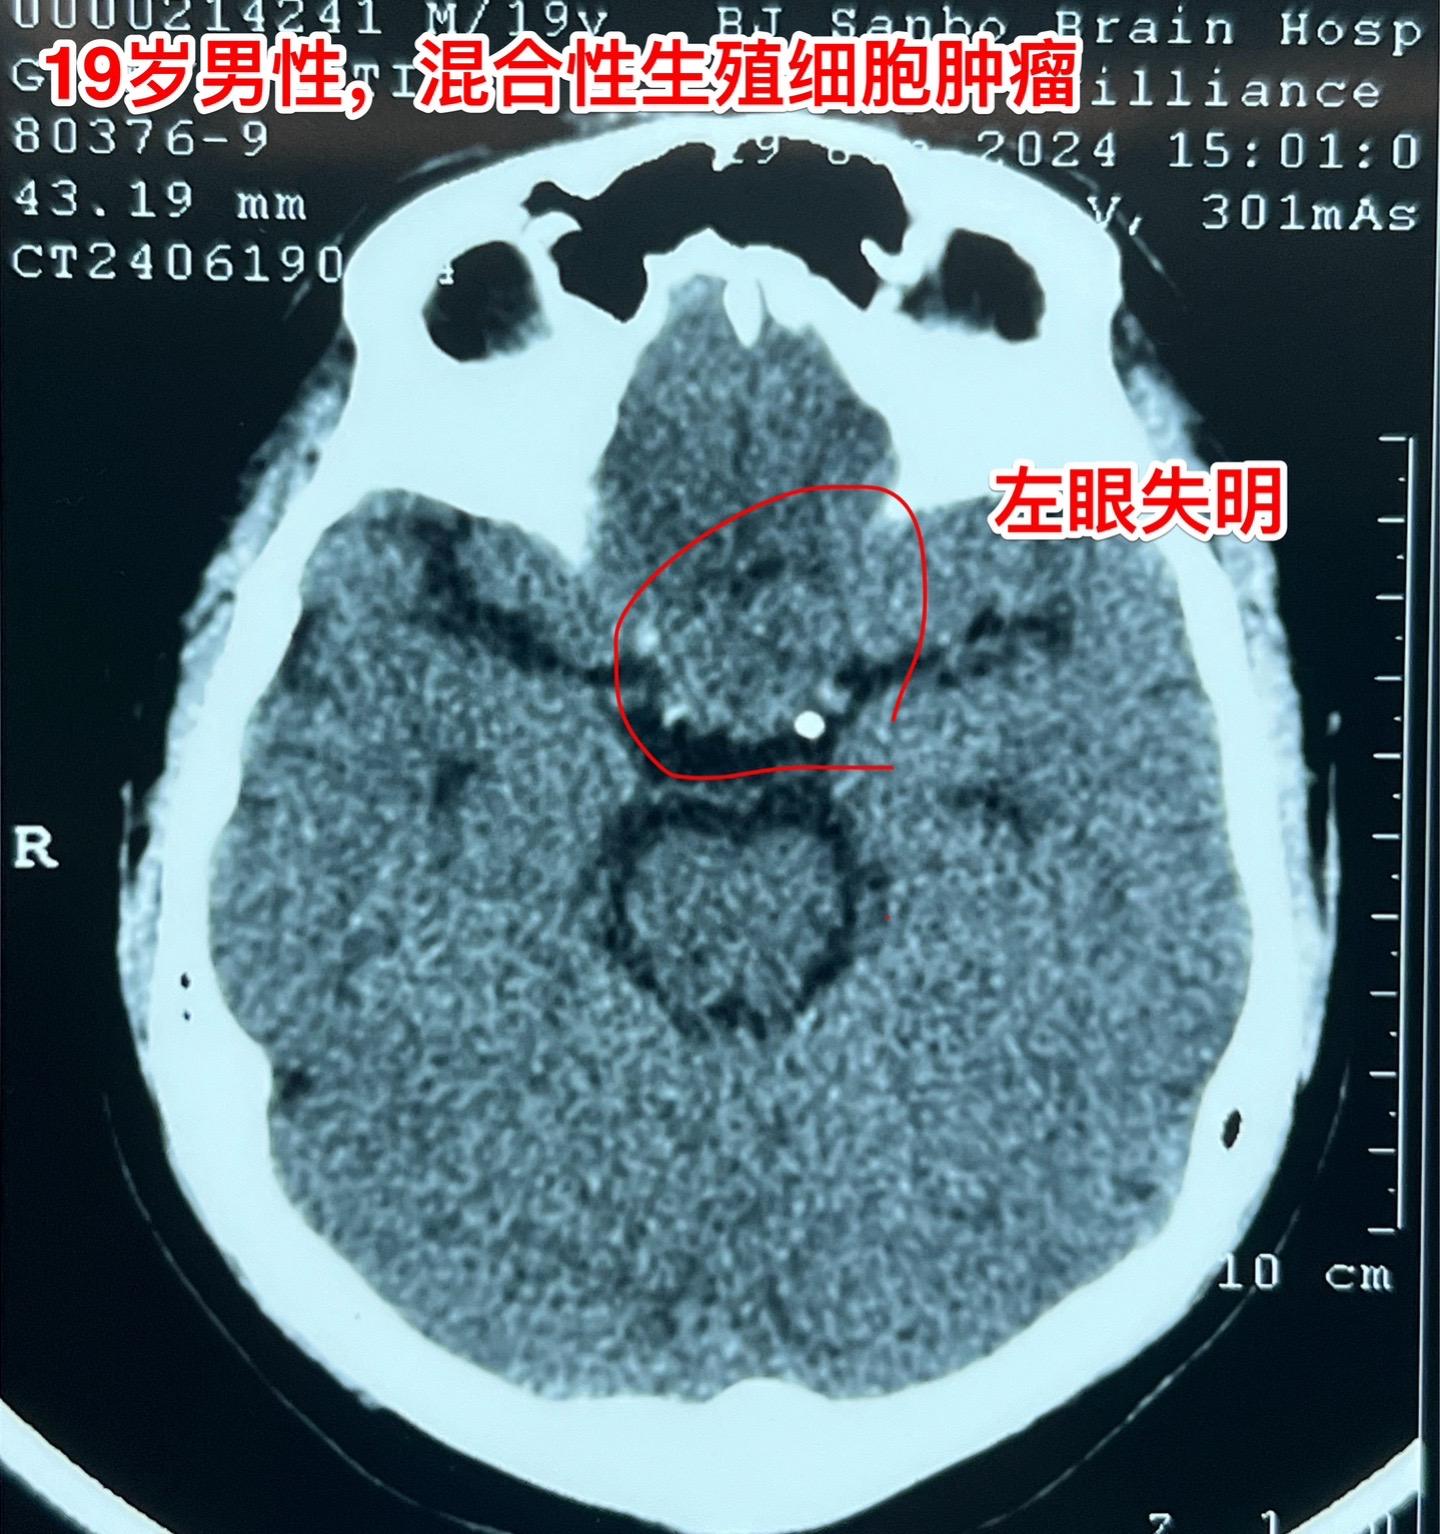

混合性生殖细胞肿瘤复发需要综合治疗。19岁莆田籍男性,三年半前还是新冠疫情期间,就因头痛发现松果体区肿瘤,怀疑是生殖细胞肿瘤,经过伽马刀治疗+化疗,肿瘤消失了,病人能正常上学。 2023年12月病人出现左眼视力下降,多饮多尿症状,复查磁共振显示鞍区肿瘤。取肿瘤活检提示是混合性生殖细胞肿瘤。化疗两个疗程,肿瘤体积稍微变小,停止化疗后肿瘤体积有增大,左眼视力呈恶化趋势,到北京三博来就医时左眼已经失明了。肿瘤的影像学资料见图。化验肿瘤标记物AFP、beta HCG均高于正常,这种情况下首选的是作